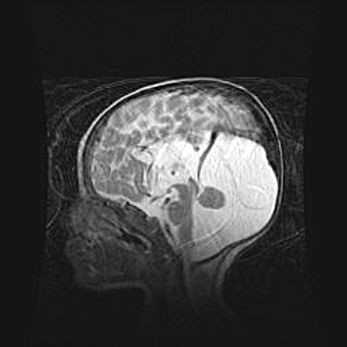

Мальформация Денди-Уокера. Киста задней черепной ямки.

Агенезия мозолистого тела.

Возраст: 2,5 месяца

Вес: 2420 г

Пол: женский

Окружность головы: 37 см

Срок гестации: 32 недели

Мальформация Денди—Уокера — редкий вид патологии ЦНС, представляющий собой врожденный порок развития каудального отдела ствола и червя мозжечка, ведущий к неполному раскрытию срединной (Мажанди) и латеральных (Лушка) апертур IV желудочка мозга. Для этогно синдрома характерна триада симптомов: гипотрофия червя мозжечка и/или полушарий мозжечка, кисты задней черепной ямки, гидроцефалия различной степени. В 70% случаев порок сочетается и с другими аномалиями головного мозга, в частности с агенезией мозолистого тела.